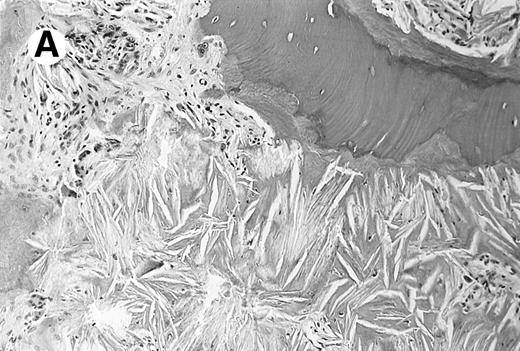

Photomicrograph of the bone marrow biopsy. (A) Oxalate crystal deposition seen adjacent to hematopoietic cells. (B) Same biopsy section viewed under polarized light showing the birefringent property of oxalate crystals.

A 23-year-old woman described left-sided abdominal discomfort and stomach bloating for 4 months. Her past medical history was significant for recurrent kidney stones, which began at the age of 9 years. She developed progressive renal failure secondary to nephrolithiasis and for the past 3 years had required hemodialysis. Five months ago she developed a painless hard mass on the distal phalanx of her left fifth finger; the mass was biopsied. The biopsy specimen was consistent with granulomatous dermatitis with birefringent crystals in the dermis. The finger mass continued to enlarge, and a repeat biopsy was taken. On physical examination there was massive hepatosplenomegaly with no lymphadenopathy or peripheral edema. There was a nontender, firm, flesh-colored nodule on her left fifth distal phalanx. Laboratory studies showed pancytopenia with a hemoglobin level of 6.3/dL, a white blood cell count of 2,600/μL, and a platelet count of 106,000/μL. Values for serum aspartate transaminase, alanine transaminase, and bilirubin were normal. Her peripheral-blood film had numerous teardrop forms compatible with myelophthisis. A bone marrow biopsy revealed extensive crystal deposition with almost complete obliteration of hematopoietic cells (Fig1). Infrared spectroscopy performed on the bone marrow biopsy and finger mass identified calcium oxalate monohydrate crystals.